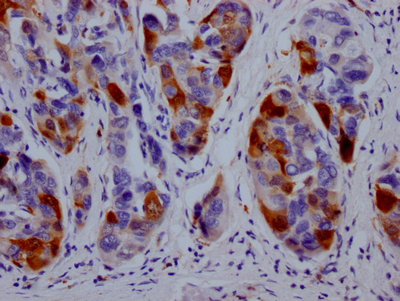

IHC image of CSB-RA264582A0HU diluted at 1:100 and staining in paraffin-embedded human liver cancer performed on a Leica BondTM system. After dewaxing and hydration, antigen retrieval was mediated by high pressure in a citrate buffer (pH 6.0). Section was blocked with 10% normal goat serum 30min at RT. Then primary antibody (1% BSA) was incubated at 4℃ overnight. The primary is detected by a Goat anti-rabbit IgG polymer labeled by HRP and visualized using 0.05% DAB.